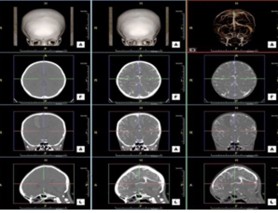

Những năm vừa qua được sự quan tâm của thủ trưởng các cấp cùng với sự đầu tư của Đảng ủy, Ban giám đốc Bệnh viện trong chẩn đoán và điều trị, bệnh viện đã trang bị nhiều máy móc hiện đại, trong đó đặc biệt có máy CT Scanner 16 Slice SIEMENS của Cộng Hòa Liên Bang Đức, cùng với sự chuyển giao kỹ thuật, công nghệ mới, các bác sỹ và kỹ thuật viên đã làm chủ hoàn toàn các kỹ thuật phức tạp mà chỉ có tuyến tỉnh và trung ương mới đáp ứng được như: Chụp CTscanner có thuốc cản quang gan ba thì, ổ bụng, lồng ngực, sọ não, hệ mạch máu bụng, chậu, chi…Trong thu dung cấp cứu, máy CT Scanner càng phát huy thế mạnh trong chẩn đoán chấn thương sọ não, chấn thương bụng kín…